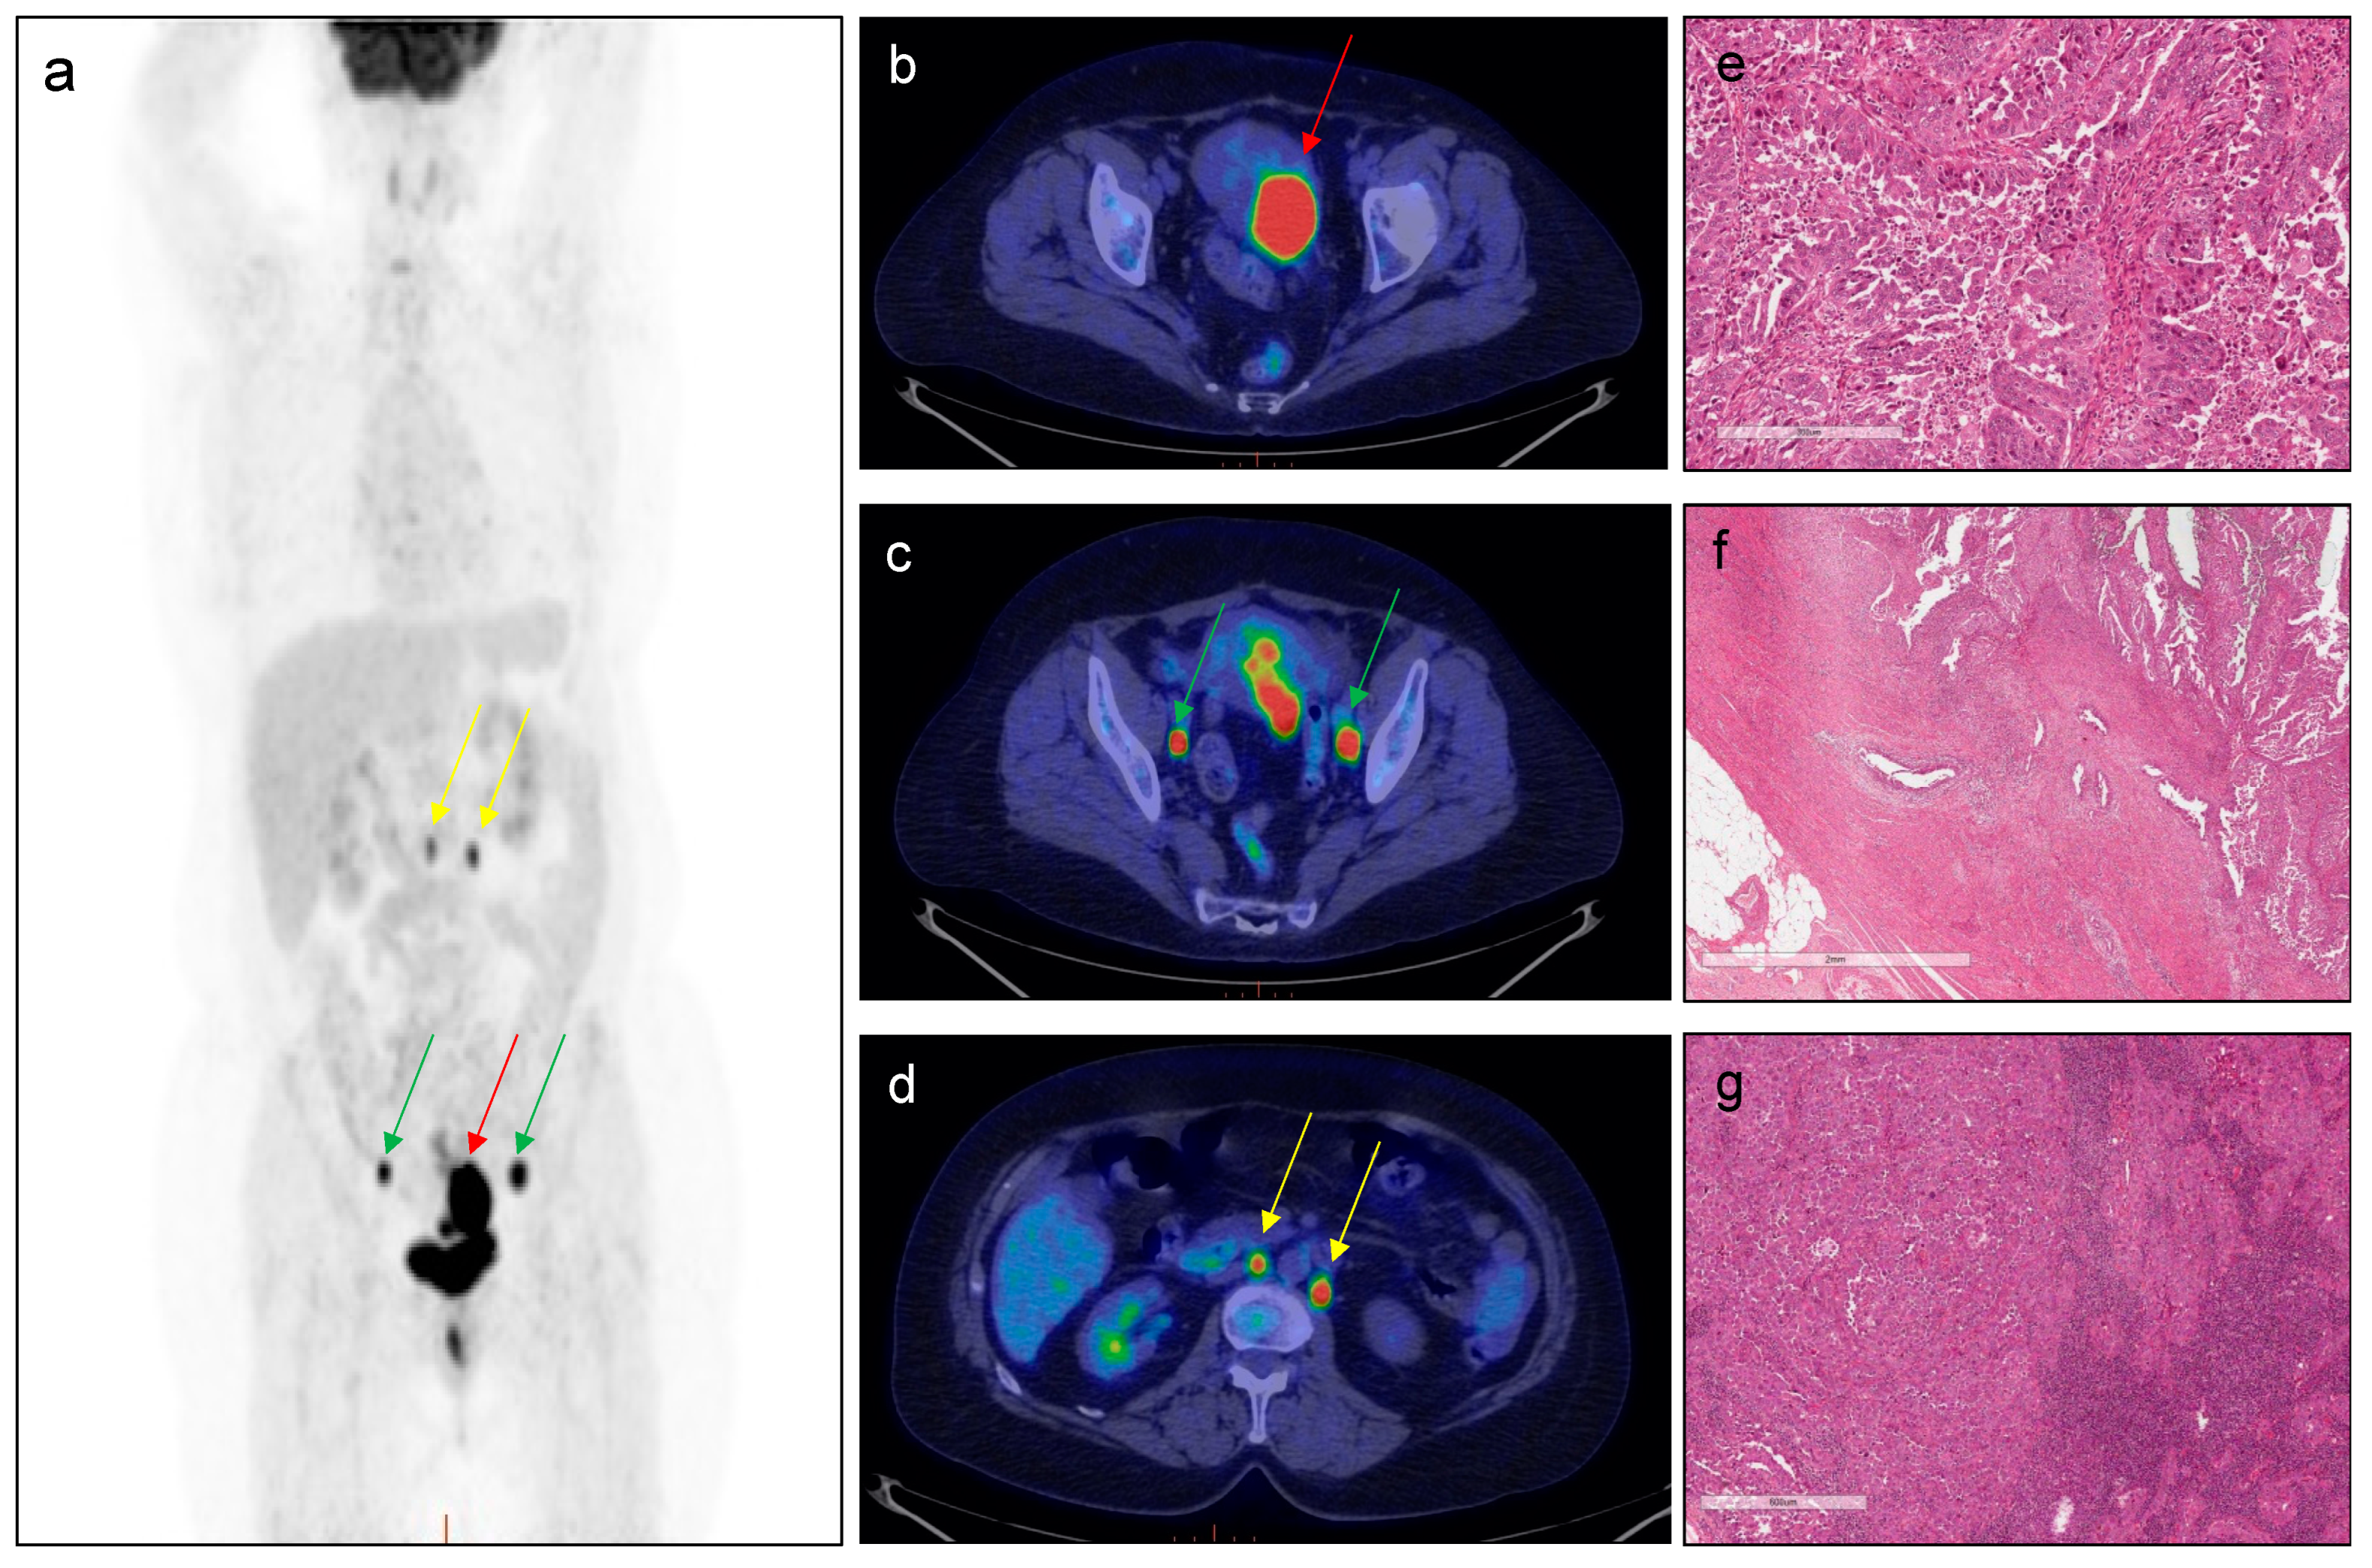

A representative case of a patient with the respective PET parameters’ values and features of EC aggressiveness is reported in Figure 3.

Figure 3. 18F–FDG PET performed for EC staging. A 71-year-old patient with endometrial cancer (Stage: III C1; Grade: 3; histotype: non-endometrioid EC; MI: 85%; risk group: high–intermediate/high; presence of LNs) who underwent 18F–FDG PET/CT for staging purpose. Red arrows indicate pathological uptake in correspondence of the primary tumour. green arrows indicate pathological uptake in correspondence of bilateral iliac–obturator lymph nodes and yellow arrows indicate pathological uptake in correspondence of lomboaortic and interaortocaval lymph nodes ((a): MIP; (b–d): transaxial PET/CT images). PET parameters of the primary tumour were as follow: SUVmax = 17.43; SUVmean = 11.82; MTV = 28.60; TLG = 338.04. Histological analysis: the tumor is constituted by large cells with a high grade of nuclear atypia and numerous mitotic figures (e). The tumoral growth is mainly in papillary projections. Myometrial infiltration (f) has a tubulo–glandular architecture with micro–papillary structure into the lumen; the way of myometrial invasion is infiltrative/destructive. Lymph nodal metastasis (g) is nodular and constituted by serous atypical cells arranged in cords and small nests.